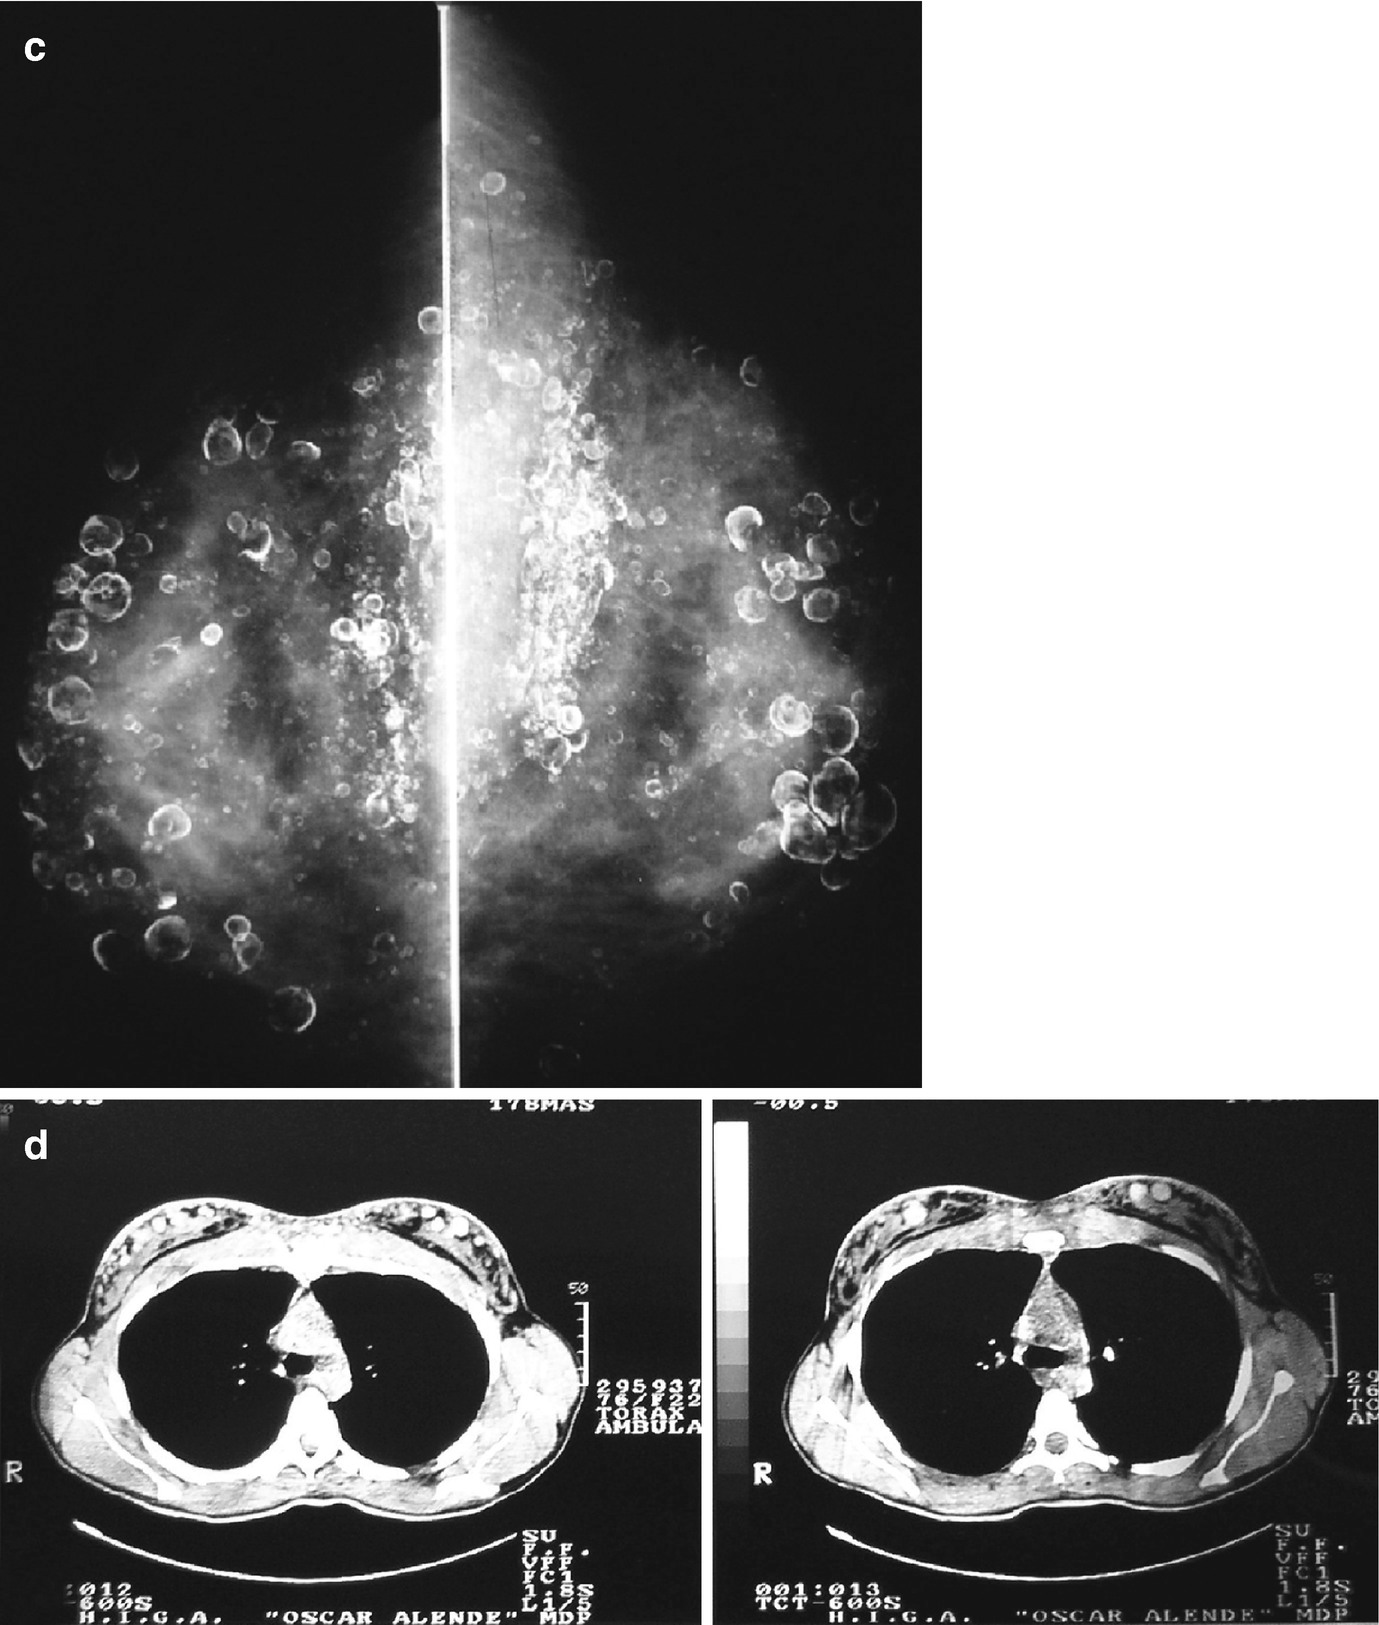

Patient deceased due to pulmonary silicone embolism during the clandestine injection of liquid silicone into her breasts. (a) Side view on the Morgagni table. (b) Front view. (c) Left breast with a puncture wound in the inferior-internal quadrant. (d) Left breast with a puncture wound in the super-external quadrant. Note the home-made bra used immediately post-injection, placed to seal the silicone in its desired location. (e) Pool of intramammary silicone found during autopsy. (f) Lung micrograph, hematoxylin-eosin stained, 10× magnification. Thrombosis of blood vessels, marked hyperemia, intra-alveolar edema, and clear vacuoles without dye affinity in the arteries and capillaries are observed. (g) Same as in (f) but at 40× magnification. (h) Kidney micrograph, hematoxylin-eosin stained at 10× magnification. Glomerular capillaries are observed with clear globules but no dye affinity. (i) Same as in (h) but with 40× magnification. (Photos: courtesy of Dr. J. Herbstein)

In the dermis, two puncture-type wounds 0.3 cm in diameter were observed, one located in the upper outer quadrant of each breast (Fig. 5.1c, d) [1], the right one larger than the left. When the area around it was compressed, a substance with an oily, transparent appearance and consistency emerged from each wound.

A sample of this transparent, oily substance, from the left breast, was sent to the chemistry laboratory for identification.

A histopathological study of the subcutaneous and muscular cell tissue of the pectoral region, as well as brain, cardiac, pulmonary, hepatic, and renal tissue was requested. The paraffin inclusion and hematoxylin-eosin staining technique yielded the following results.

The brain had areas of demyelination, edema, and perivascular hemorrhage. Both lungs exhibited blood vessel thrombosis, accentuated hyperemia, intra-alveolar edema, and clear vacuoles without dye affinity for hematoxylin-eosin in either arteries or capillaries (Fig. 5.1f, g) [1]. Sinusoidal spaces of the liver were congested, with fatty degeneration in the periphery of the central vein. The heart had preserved histological architecture. A fragment of fatty tissue that covered the muscular tissue extracted from the pectoral region exhibited cystic areas with gelatinous content and areas with clear vacuole infiltrates, but no dye affinity for hematoxylin-eosin. The kidney had glomerular capillaries, with clear globules and no dye affinity for hematoxylin-eosin (Fig. 5.1h) [1]. The changes described here indicate the presence of multiple fat emboli. The chemical laboratory reported that the oily substance sent in for analysis had physical characteristics consistent with silicone.”

The above case illustrates how that injecting silicones for cosmetic purposes may cause pulmonary thromboembolism, which triggered immediate death in the above-described patient. The mechanism behind the pulmonary embolism could be related to the local pressure induced by the injection of large volumes of substance, to the local massage that is frequently associated with this procedure, or to migration or direct injection into vessels. Of these, the last mechanism seems to be what triggered death in the above-presented case.